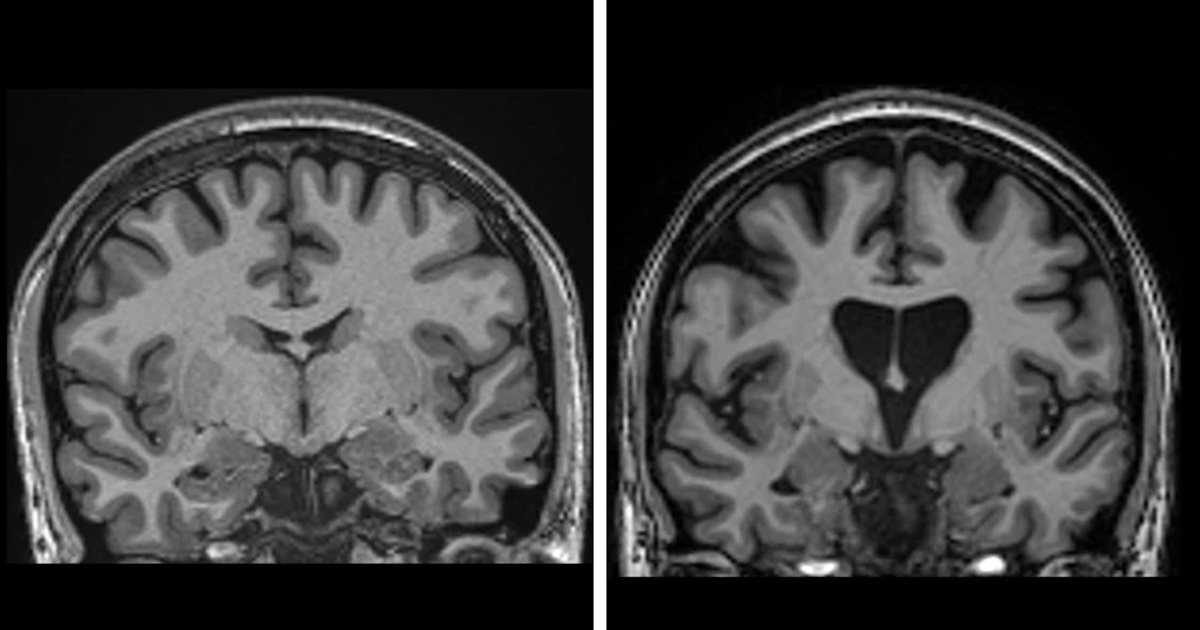

Affecting around 41,000 people in the US, and with 200,000 more genetically predisposed to developing it, Huntington’s Disease is a devastating condition that causes irreversible brain decline and premature death.

With symptoms often becoming present in a person’s 30s or 40s, the condition then causes rapid decline due to the progressive death of brain cells, with patients usually dying within the next twenty years.

During the surgery – a pioneering type of gene therapy which targets the huntingtin gene in the DNA – a safe virus is infused into the brain.

This virus delivers tiny DNA into brain cells, which then learn to replicate the gene-silencing DNA sequence, meaning that levels of huntingtin in the brain will be reduced, and its brain cell killing properties disabled.

What’s more, the trial was an unprecedented success, with 75% of patients seeing a slowing of the disease, and some patients having remarkable recoveries.